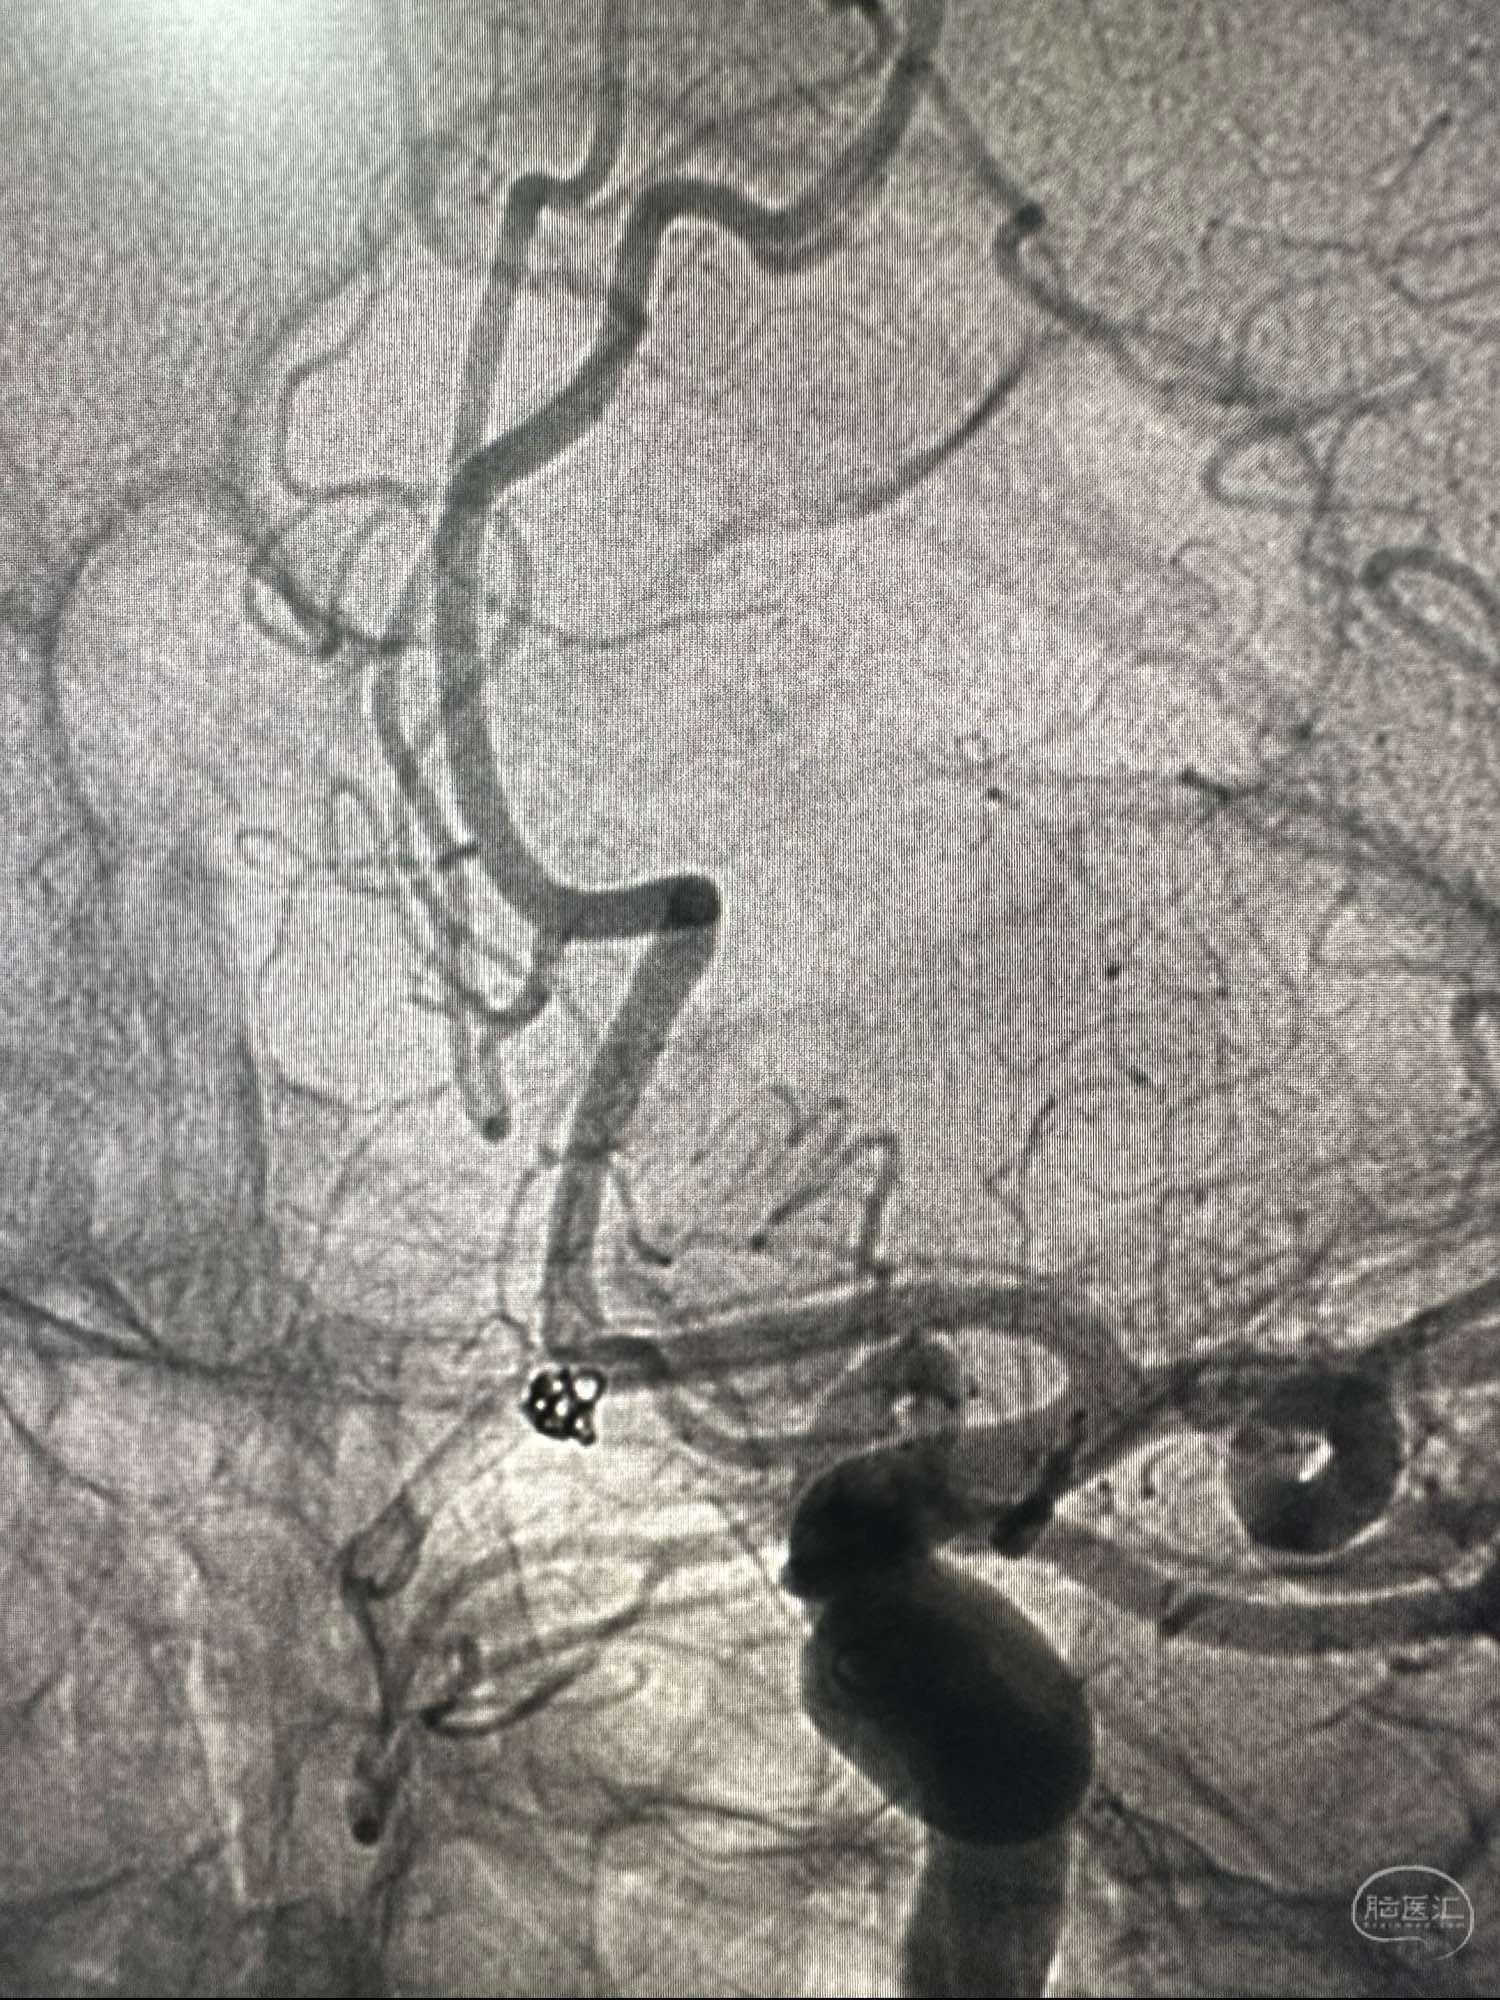

左侧颈内动脉路途,cook长鞘加上6F的银蛇中间导管

Sl_10的支架导管保护下。Enchon-10进入动脉瘤,一枚圈处理cosmos3D的圈2.5*4